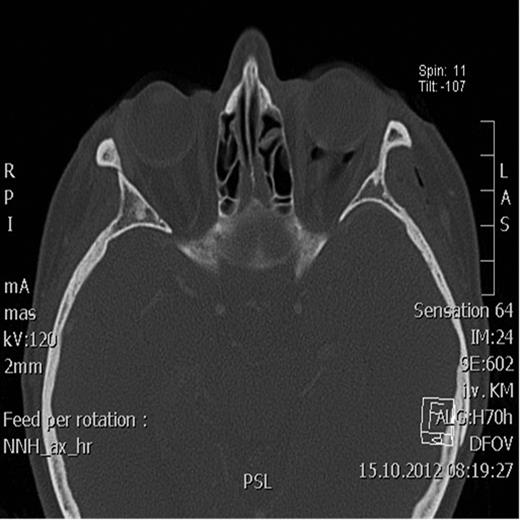

Owing to the clinical findings and the severity of the symptoms, surgical decompression was performed under general anesthesia. Lateral blepharoplasty and transconjunctival incisions were made (Fig. 3). The left orbital floor was exposed, revealing a non-dislocated bone defect, without herniation of the periorbital tissue. The surgical management with orbital drainage produced excellent results, with sudden resolution of the proptosis and a postoperative improvement in visual acuity, confirmed by further ophthalmological evaluation (Figs 4–5). The patient was put on amoxicillin and clavulanic acid every 8 h, and advised not to blow her nose vigorously and to use a nasal decongestant.

Postoperative axial CT scan showing normal position of the bulbus.